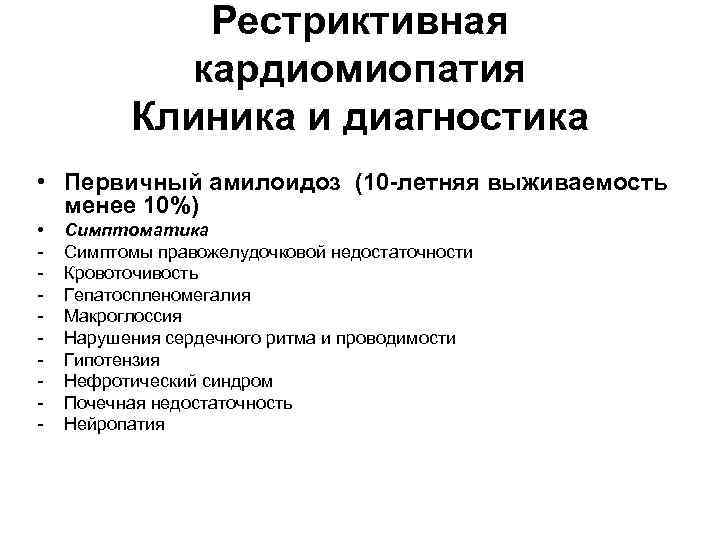

Рестриктивная кардиомиопатия Клиника и диагностика • Первичный амилоидоз (10 -летняя выживаемость менее 10%) • - Симптоматика Симптомы правожелудочковой недостаточности Кровоточивость Гепатоспленомегалия Макроглоссия Нарушения сердечного ритма и проводимости Гипотензия Нефротический синдром Почечная недостаточность Нейропатия

Рестриктивная кардиомиопатия Клиника и диагностика • Первичный амилоидоз (10 -летняя выживаемость менее 10%) • - Симптоматика Симптомы правожелудочковой недостаточности Кровоточивость Гепатоспленомегалия Макроглоссия Нарушения сердечного ритма и проводимости Гипотензия Нефротический синдром Почечная недостаточность Нейропатия